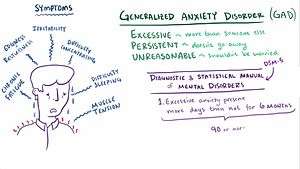

Generalized anxiety disorder (GAD) is an anxiety disorder characterized by excessive, uncontrollable and often irrational worry, that is, apprehensive expectation about events or activities.[1] This excessive worry often interferes with daily functioning, as individuals with GAD typically anticipate disaster, and are overly concerned about everyday matters such as health issues, money, death, family problems, friendship problems, interpersonal relationship problems, or work difficulties.[2][3] Individuals often exhibit a variety of physical symptoms, including fatigue, fidgeting, headaches, nausea, numbness in hands and feet, muscle tension, muscle aches, difficulty swallowing, excessive stomach acid buildup, stomach pain, vomiting, diarrhea, bouts of breathing difficulty, difficulty concentrating, trembling, twitching, irritability, agitation, sweating, restlessness, insomnia, hot flashes, rashes, and inability to fully control the anxiety (ICD-10).[4] These symptoms must be consistent and ongoing, persisting at least six months, for a formal diagnosis of GAD.[1][2]

The diagnostic criteria for GAD as defined by the Diagnostic and Statistical Manual of Mental Disorders DSM-5 (2013),[1] published by the American Psychiatric Association, are as follows:

A. Excessive anxiety and worry (apprehensive expectation), occurring more days than not for at least 6 months, about a number of events or activities (such as work or school performance).

B. The individual finds it difficult to control the worry.

C. The anxiety and worry are associated with three (or more) of the following six symptoms (with at least some symptoms having been present for more days than not for the past 6 months):